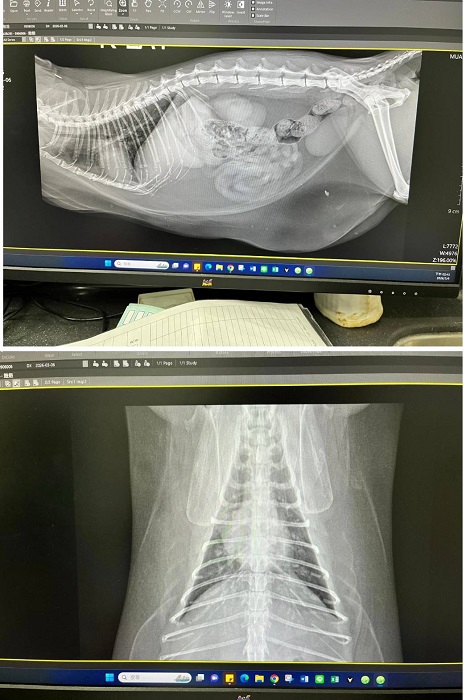

2026年3月初遷移回台北安養之家的妞妞,因照護員觀察到妞妞腹部腫大下垂,謹慎起見於是安排2026年3月6日於沐恩醫院進行看診,拍攝腹腔X光檢查,顯示胸腹部均為脂肪,屬於背部脂肪不太生成集中於腹部的體質,可不用擔心。X光看起來胰臟較大,不過質地沒有異常。同時針對胰臟較大進行超音波檢查,確認無異常。血檢也均正常。鎮靜後林院長幫妞妞修剪指甲及觸診,頭部有一側抓破皮,再請留意妞妞會不會時常抓癢。妞妞整體來說很健康,體重略重再觀察即可。本筆醫助是妞妞於2026年3月6日於沐恩醫院的醫療費用,包含看診、血檢、胸腔X光及超音波的費用。

2026/3/6 妞妞 沐恩 林院長

體重:4.800kg (上次2020/7/28是4.065kg)

一、看診情形

1.妞妞檢查腹部下垂球狀。

2.拍攝腹腔X光片,顯示胸腹部均為脂肪,

屬於背部脂肪不太生成會集中於腹部的體質,可不用擔心。

X光看起來胰臟較大,不過質地沒有異常。

3.針對胰臟較大進行超音波檢查,確認無異常。

4.血檢均正常。

5.鎮靜後林院長幫妞妞修剪指甲及觸診,頭部有一側抓破皮,

再請留意妞妞會不會時常抓癢。

6.妞妞整體來說很健康,體重略重,再觀察即可。

二、回診

有需要再約診